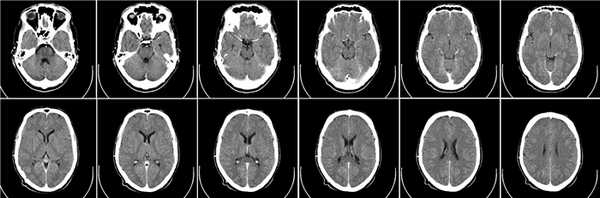

(Слева) На рентгенограмме верхних шейных позвонков в боковой проекции определяется незамкнутая костная дуга над отверстием позвоночной артерии в С1, типичная для аномалии Киммерле (неполный вариант).

(Справа) На рентгенограмме верхних шейных позвонков в боковой проекции визуализируется замкнутая костная дуга над отверстием позвоночной артерии в С1, характерная для классической аномалии Киммерле (полный вариант).

2. Рентгенография при аномалии Киммерле:

• Рентгенологические признаки:

о Полный или частичный костный мостик над отверстием позвоночной артерии в С1

Рентгенография

Определяется наличие замкнутого костного канала для позвоночной артерии или очень редко незамкнутого. В старшей возрастной группе возможны сопутствующие дегенеративно‐дистрофические изменения шейного отдела позвоночника.

Рентгенография ШОП (боковая проекция). Дополнительное костное кольцо в области задней дужки С1 (аномалия Кимерли)